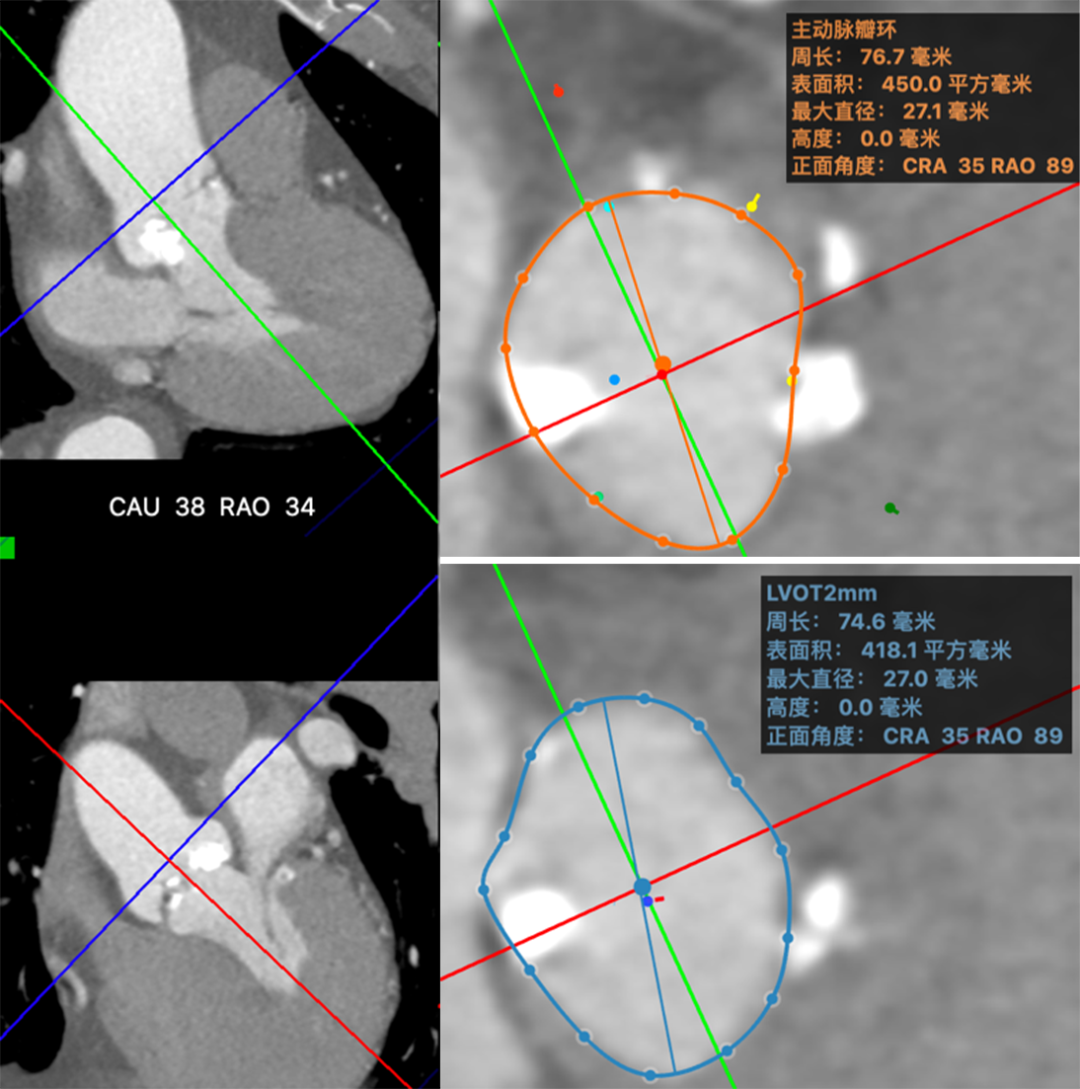

术前CT评估

主动脉瓣评估:患者为三叶式主动脉瓣,瓣叶可见多发斑点团片结节状钙化,瓣环见粗大钙化,瓣环周长77 mm,瓣口开放面积61 mm²,左室流出道见条片状钙化